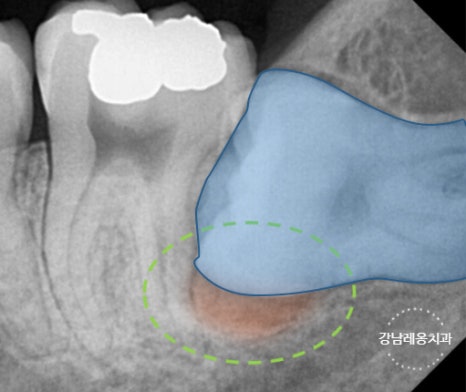

✅ 아래턱 신경과 매우 가까운 위치의 사랑니

✅ 염증이나 낭종을 동반된 경우

고난도 케이스 경험 다수

최소절개

하루 발치 최대 60개

사랑니 발치로 강남레옹치과에 방문해주시는

40~50%가 수평/매복 사랑니이며

아래와 같은 고난도 케이스도

충분한 상담을 통해

사랑니 진료를 진행하고 있습니다.